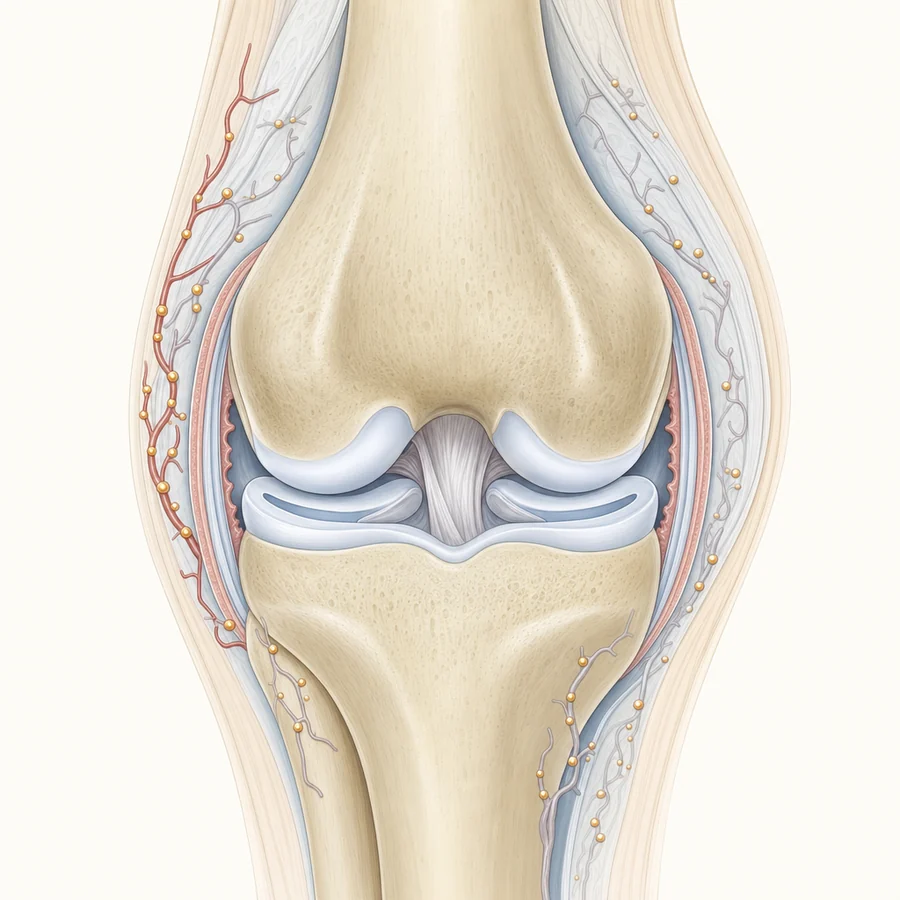

GAE for Knee Pain

Knee-targeted embolization

Genicular Artery Embolization (GAE) treats knee osteoarthritis pain without surgery. Step through the process or watch the video.

In a knee with osteoarthritis, the inflamed joint lining (the synovium) grows extra, abnormal blood vessels. That excess blood flow feeds ongoing inflammation, which is a major driver of knee pain.